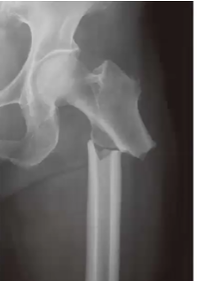

Tipo de fractura de esta radiografia

Subtrocanterica femoral

Mecanismo de lesion de esta fractura

Lesiones de alta energia en jovenes (Trafico, caidas, armas de fuego)

Fracturas patologicas

Lesiones de baja energia (caida de propia altura) en ancianos

Clasificacion de Fielding (para fracturas subtrocantericas de femur)

1. Tipo I → altura del trocánter menor.

2. Tipo II → menos de 2.5 cm por debajo del trocánter menor.

3. Tipo III 2.5 a 5 cm por debajo del trocánter menor.

Tratamiento de esta fractura

Clavo intramedular con pernos de segunda generacion

Implantes si no hay recursos